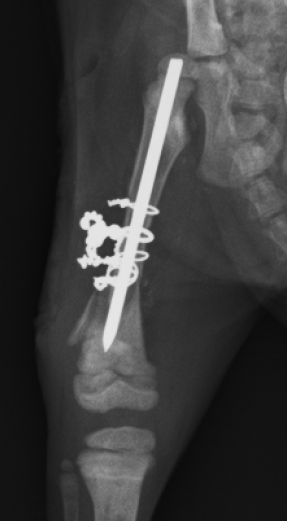

レントゲンにあるように

複雑な骨折になっており、細かい骨も周りに散らばり

靭帯が損傷し膝の可動域が現在ない状態で曲がらない。

という状態でした。

まずはレントゲンの写真をご覧ください

6月17日でのレントゲンです

固着してきてますが、骨の欠片が飛び出ているようになっています。

そして抜糸当日の24日

完全に固着していないものの、飛び出した骨も安定してきており

先生の判断で抜糸という経緯になりました。

治療・手術対象

ミント(猫、雑種、2か月、メス)

治療・手術内容

右後ろ脚の複雑骨折及び靭帯損傷